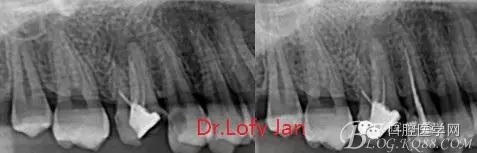

前言:自己做的一些曲面斷層片在未試尖根管治療中的病例整理,發(fā)現(xiàn)問題很多包括自身的,技術(shù)的,還有設(shè)備的問題,予以總結(jié)整理并期待進(jìn)一步提高。

根管治療術(shù)是牙體牙髓疾病治療中最復(fù)雜和最關(guān)鍵的治療項目。根管充填材料抵達(dá)根尖、并能嚴(yán)密堵塞根尖孔,是確保根管治療效果的關(guān)鍵指標(biāo)。為了保證根管充填到位,醫(yī)生需要在術(shù)前照牙片以了解牙根根管的數(shù)量、彎曲程度和長度,在術(shù)中有時需要插針照牙片來精確測量根管長度,術(shù)后必須照牙片以確定是否根管充填到位,如果欠填或超填,就需要重新充填、重新照牙片確認(rèn),直到根管充填到位。所以,在患者接受根管治療時有時會反復(fù)照牙片。

病例分析:曲面斷層片在x線輔助診斷與檢查中目前大多數(shù)文獻(xiàn)和著作都建議只能作為初診拍片檢查手段,不能作為終末疾病的確診與手術(shù)療效的評價指標(biāo),臨床大部分中小型門診都因為設(shè)備不齊全導(dǎo)致信息偏差很大。